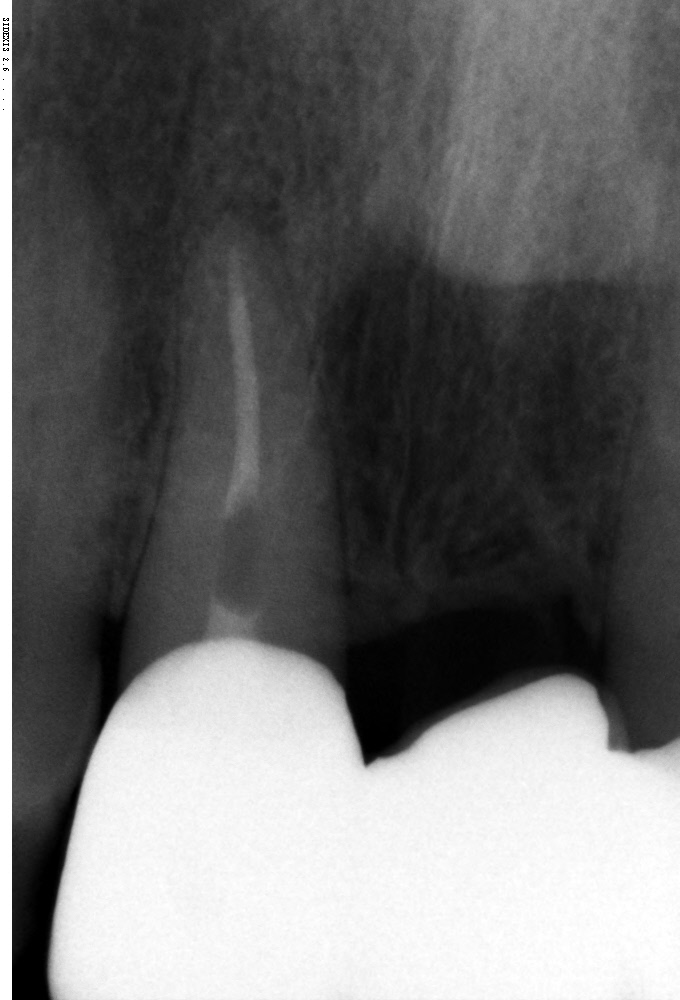

in oktober 2022 heb ik een nieuwe brug laten plaatsen vanwege doorschijnen van het metalen fundament van de 15 jaar oude brug.

Nadat de nieuwe brug is geplaatst ( keramisch fundament), verscheen er een zwart randje tussen de brug/tandvlees en de onderliggende pijler.

De tandarts heeft de onderliggende pijler gebleekt, dat was verholpen.

Alleen na verloop van tijd is het zwarte randje weer.. Ben door mijn tandarts verwezen naar een Paradontoloog voor tandvleestransplantatie. De paradontoloog vond dit geen mogelijke oplossing.

Het zwarte randje is van de bestaande tand, deze heeft in het geleden al een wortelkanaal behandeling gehad. Tandvlees transplantatie is niet mogelijk om dat het tandvlees weer zal optrekken ( gevoelig). Paradontoloog wil mijn gebit herstellen, zodat mijn kiezen weer normaal op elkaar staan. Ik klem en knars ook…, waardoor brug er niet beter op zal worden en in de loop van de tijd meer naar voren komt te staan..